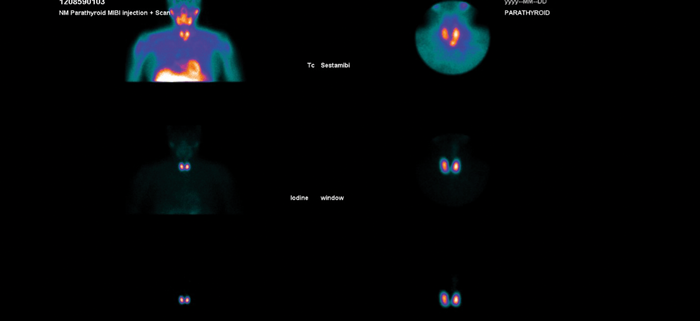

Figure 1: Dual isotope sestamibi scan showing evidence of a left inferior parathyroid adenoma.

Once the diagnosis is confirmed, preoperative localising studies can help to target the potential parathyroid adenoma. A dual isotope 123 iodine / 99mTc sestamibi scan helps to localise the parathyroid adenoma - if this is positive (see Figure 1) a parathyroid USS can be performed and, if both scans are concordant with the location of the abnormal gland, a targeted approach can be made by a unilateral neck exploration (UNE) or focused single gland approach. A USS is useful also if there is a palpable thyroid nodule so that this can be assessed preoperatively (with fine needle aspiration if required). If imaging fails to localise preoperatively and I think that the neck exploration is going to be awkward (short stout neck), or if the patient has autoimmune thyroiditis (can be difficult with surrounding lymph nodes and atrophic thyroid), I may consider a preoperative 4D CT scan to aid localisation. Patients with non-localised imaging will require a bilateral neck exploration (BNE).